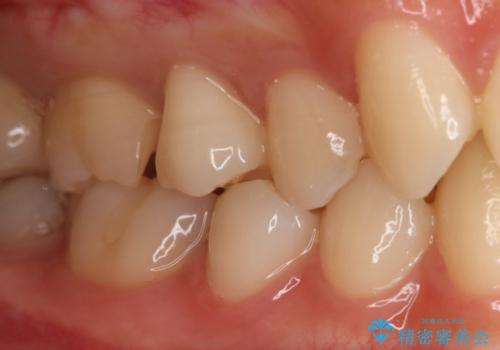

- 右上6番の保険材料で詰められた部分をセラミックにやり変え希望の患者様です。

切削量などを考慮し、セラミックインレーでの治療を選択しました。

う蝕が深くまで進行していたので、全て除去した上でCR裏層を行い形成、印象を行っています。